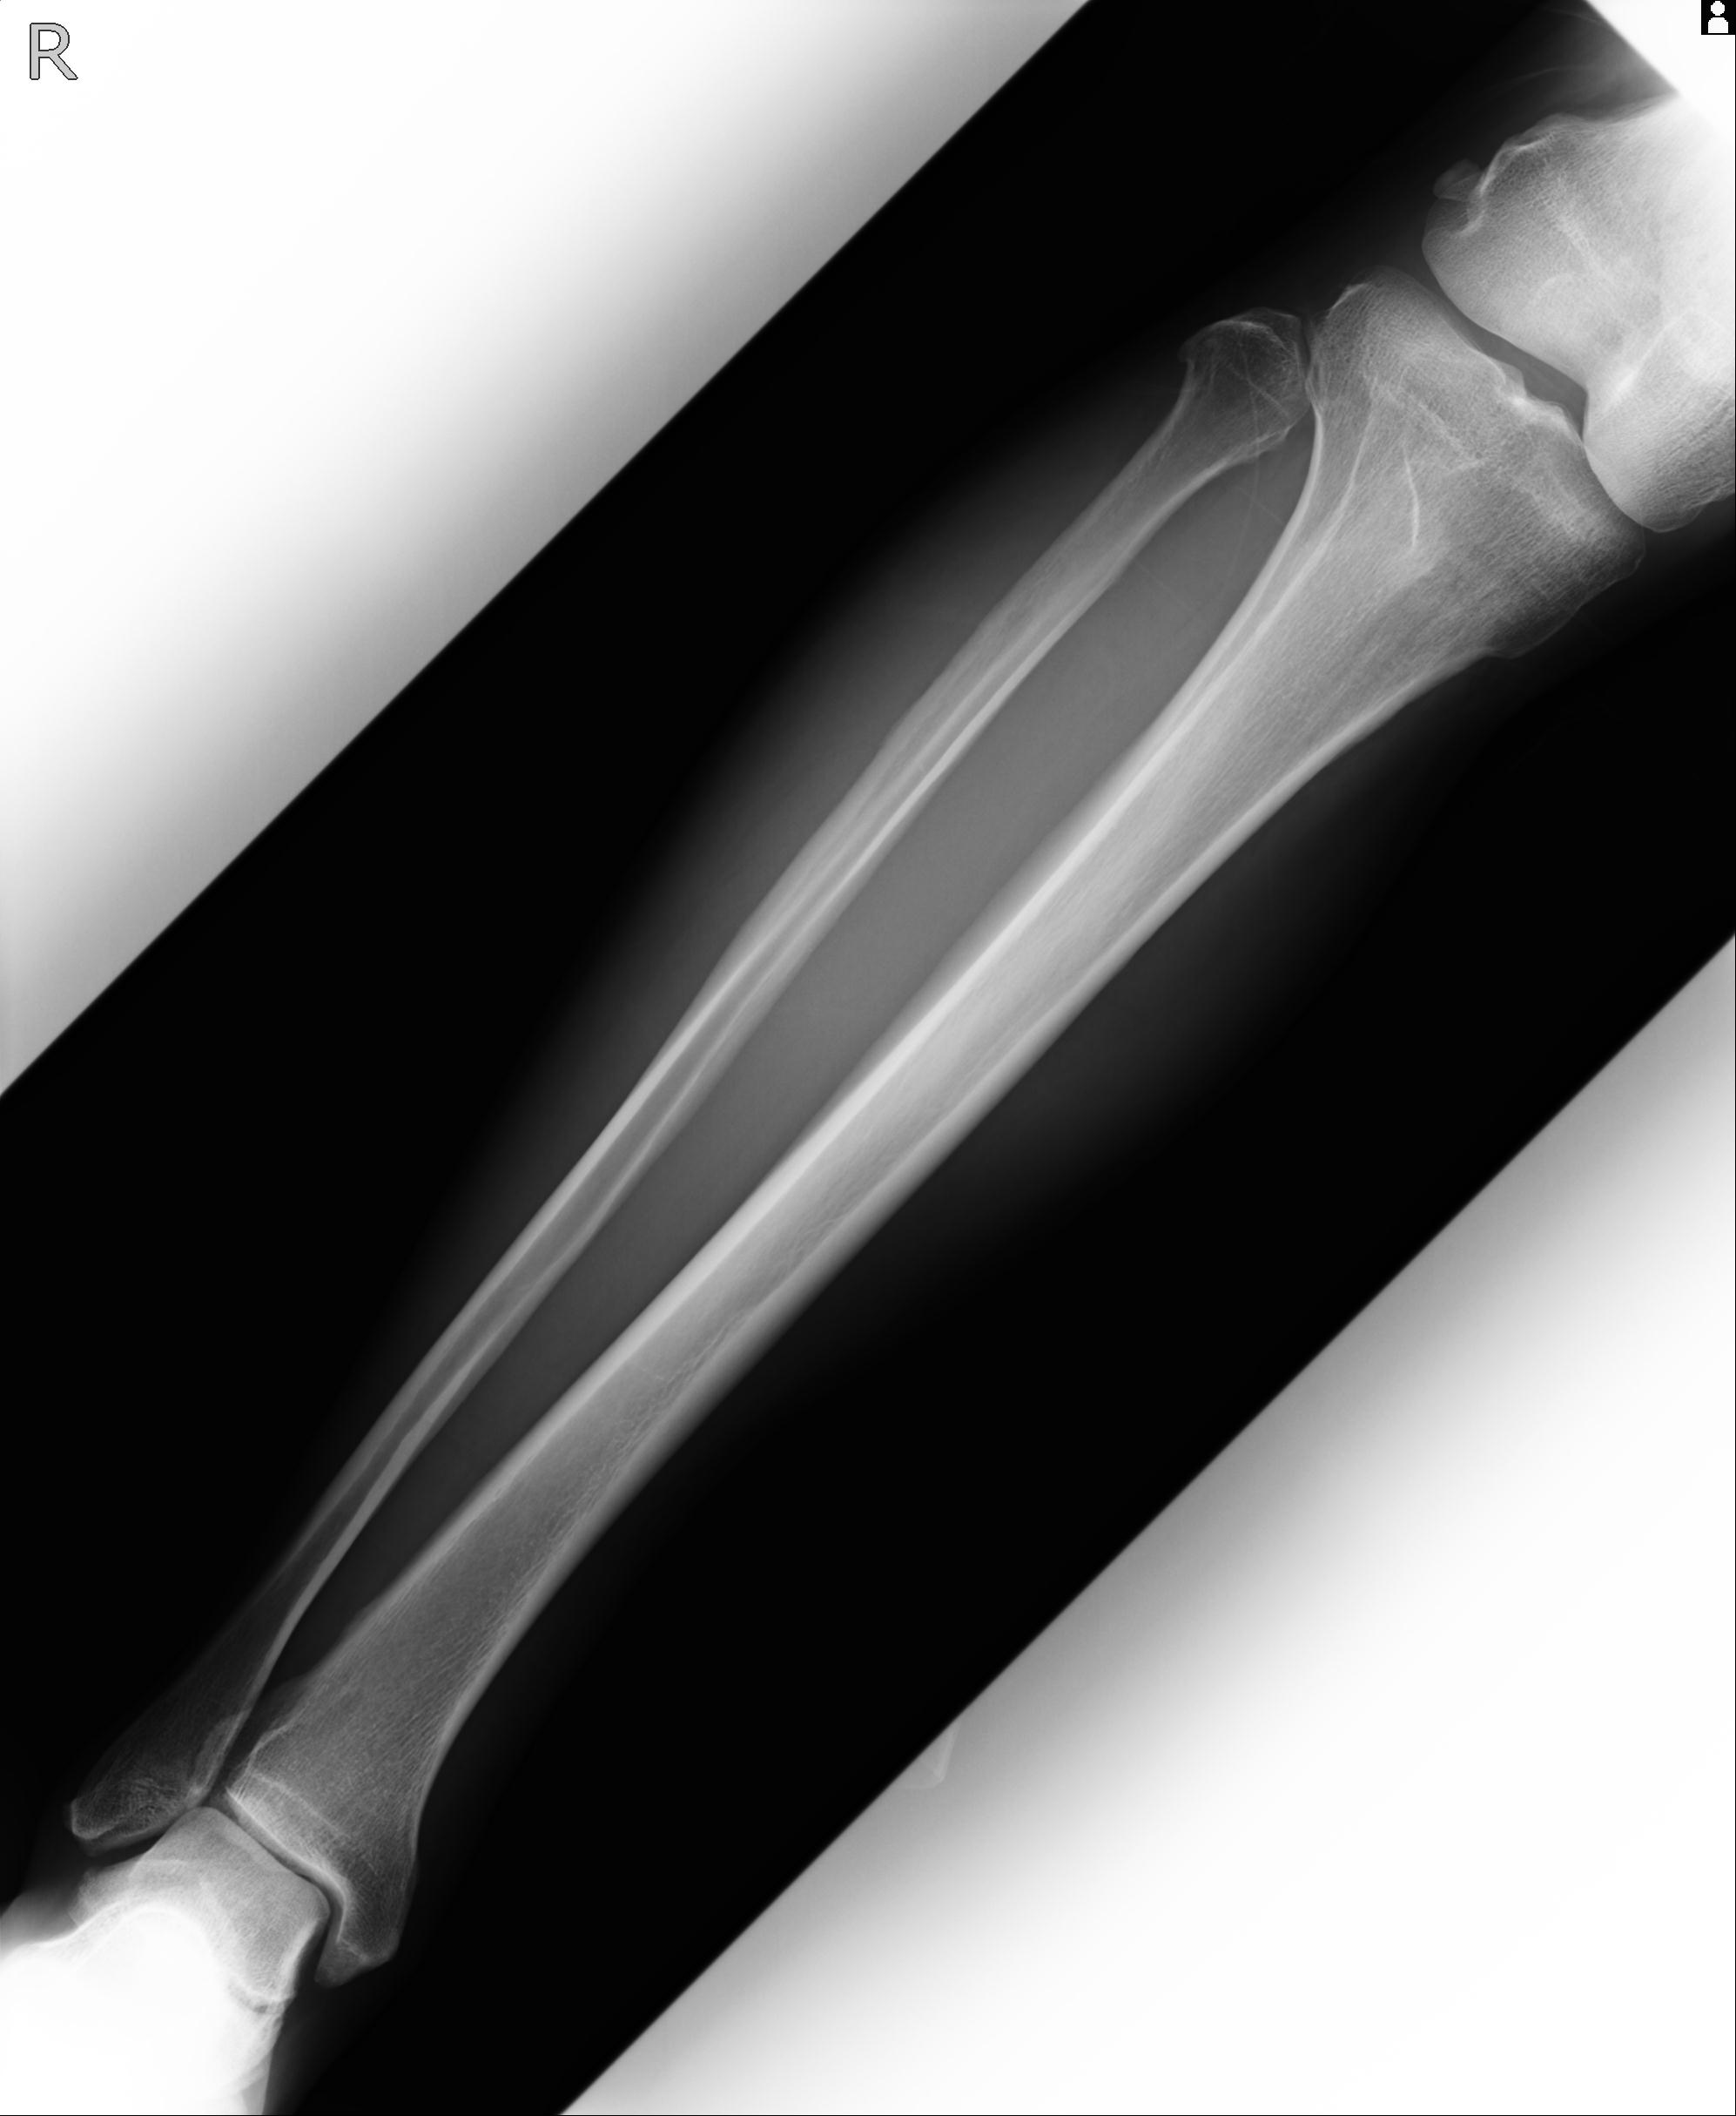

91983 11/16 左膝 2R 11/18 2R 55歳男性 脛骨骨切り術